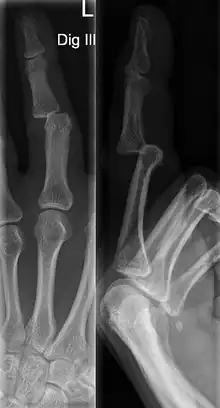

DIP dislocations are much less common than PIP dislocations.[3] This is thought to be due to the increased stability of the DIP joint,[15] though not for certain.[2] Dislocations can be categorized based on the direction that the fingertip moves in relation to the knuckle.[6] If in the direction of the palm, it is a volar dislocation. If in the direction of the back of the hand, it is a dorsal dislocation.[6] If in the direction to either side, it is a lateral dislocation.[2] Of the three, dorsal dislocations are most common.[6] Dorsal dislocations of the PIP commonly lead to volar plate damage.[2]

Dislocations are often visually obvious due to joint deformity.[2] Therefore, x-rays may or may not be utilized in the diagnosis of a suspected dislocation. Though, they can provide feedback on post-reduction status if attempted prior to formal medical evaluation.[2] Dislocations may also be complicated by a tandem fracture.[5] These cases may necessitate a visit to a hand surgeon for surgery.[2]

Dislocations are treated differently depending on the type.[4] Regardless, closed reduction is the usual first step.[6] This is where the joint is realigned without the need for surgery. For a dorsal dislocation, the fingertip is pulled while applying palmar pressure to the distal bone and dorsal pressure to the proximal bone.[22] Following reduction, movement of the joint should be tolerable.[6] Repeat X-rays are standard to confirm proper joint setting.[22] Next, the finger is splinted while slightly bent to prevent over-extension of the joint.[6] If hyperextending the joint is too painful or causes the skin to turn pale, the finger should be splinted straight.[3] Dorsal PIP and DIP dislocations should be splinted for 2-3 weeks.[22] Limited movement of the finger is recommended soon after injury to limit loss of range of motion.[3]

Lateral dislocations often require open reduction, though closed reduction can be attempted.[24] Closed reduction is attempted with the wrist extended and finger flexed at the base. The dislocated bone is then pushed back towards the joint. After reduction, X-rays are used to assess joint stability and a straight splint is placed for 2-3 weeks.[22] If closed reduction is initially difficult, it may be necessary to numb the joint to relax it and the individual. Open reduction may also be required in rare cases of dorsal and volar dislocations.[6] If post-reduction X-rays of the dislocation show misalignment of the joint or bone, a fracture may be present. Such cases may also require surgery.[3]